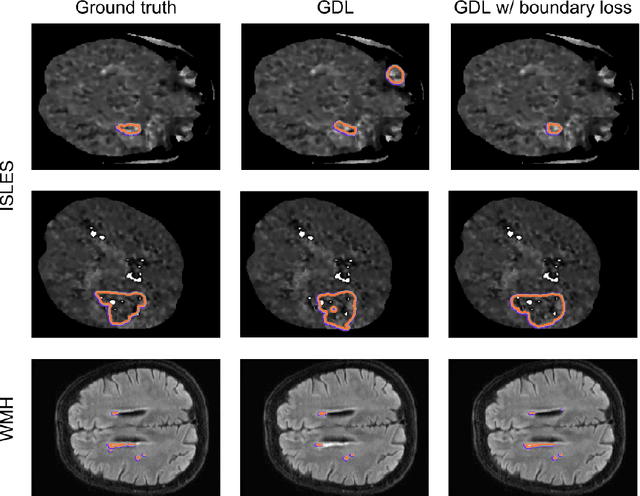

Abstract:Widely used loss functions for convolutional neural network (CNN) segmentation, e.g., Dice or cross-entropy, are based on integrals (summations) over the segmentation regions. Unfortunately, it is quite common in medical image analysis to have highly unbalanced segmentations, where standard losses contain regional terms with values that differ considerably --typically of several orders of magnitude-- across segmentation classes, which may affect training performance and stability. The purpose of this study is to build a boundary loss, which takes the form of a distance metric on the space of contours, not regions. We argue that a boundary loss can mitigate the difficulties of regional losses in the context of highly unbalanced segmentation problems because it uses integrals over the boundary between regions instead of unbalanced integrals over regions. Furthermore, a boundary loss provides information that is complementary to regional losses. Unfortunately, it is not straightforward to represent the boundary points corresponding to the regional softmax outputs of a CNN. Our boundary loss is inspired by discrete (graph-based) optimization techniques for computing gradient flows of curve evolution. Following an integral approach for computing boundary variations, we express a non-symmetric L2 distance on the space of shapes as a regional integral, which avoids completely local differential computations involving contour points. Our boundary loss is the sum of linear functions of the regional softmax probability outputs of the network. Therefore, it can easily be combined with standard regional losses and implemented with any existing deep network architecture for N-D segmentation. Our boundary loss has been validated on two benchmark datasets corresponding to difficult, highly unbalanced segmentation problems: the ischemic stroke lesion (ISLES) and white matter hyperintensities (WMH).